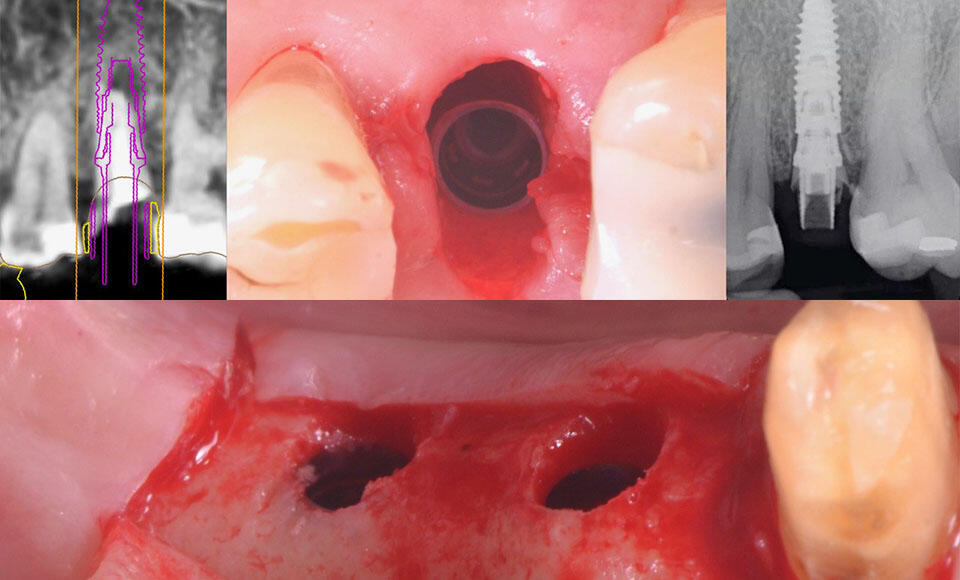

Socket Preservation oggi, approccio mini invasivo e risultati predicibili

Vediamo insieme procedure e passaggi di una tecnica riproducibile dal clinico, grazie a protocolli definiti e consolidati.

Influenza del profilo di emergenza nella Zero Bone Loss

Il profilo di emergenza della protesi su impianti risulta essere un fattore importante per ampliare in modo significativo il margine di successo in un intervento di implantologia con Zero Bone Loss.

Il posizionamento implantare: chiave di volta per una implantoprotesi ottimale

La Zero Bone Loss è la condizione ideale in cui, inserito l’impianto dentale, non si verifica riassorbimento osseo in nessun caso. Per raggiungere tale obiettivo, la profondità di posizionamento dell’impianto è un fattore fondamentale.

Zero Bone Loss: come limitare la perdita di osso intorno agli impianti?

Analizziamo insieme i fattori per interventi d’implantologia con elevata stabilità ossea senza regressioni.